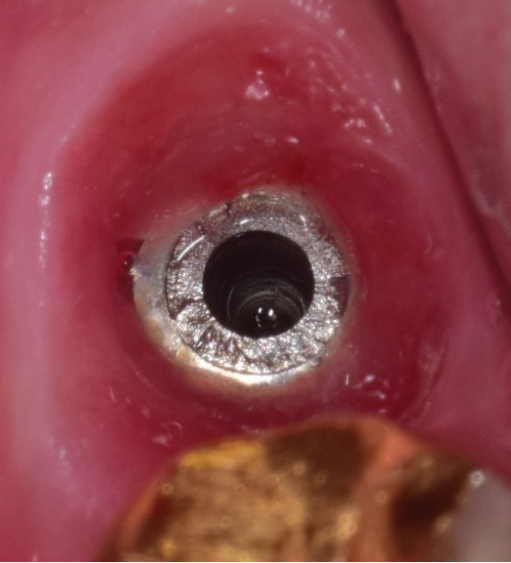

Fig. 4.

곧게 핀 익스플로러 팁으로 역회전하기

jkda-2026-64-2-006f4.jpg

1) 보철물연결나사 제거

임플란트연결나사는 보통 30N으로 채결되어 구강내에서 오랜기간을 유지하게 되는데 사용기간동안 반복되는 진동으로 풀리는 경우가 생길 수 있다. 이런 경우에는 보촐물의 동요도를 인지하게 되는데 서둘러서 치과를 방문하여 다시 조여주면 큰 문제가 없지만 방치하게 되면 피로파절이 발생하게 된다. 이때는 일단 먼저 보철물을 먼저 제거하고 파절된 나사를 제거하면 된다. 연결나사는 초음파기구로 역회전을 주면서 돌리면 조금씩 밀려나오게 되는데(Fig. 3) 이때 곧게 핀 익스플로러를 이용할 수도 있다(Fig. 4).